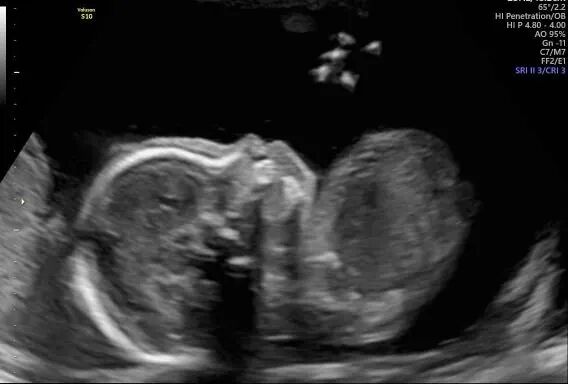

爱妈D已经怀孕11周了,她即将从诊所“毕业”。从匹配成功开始,爱妈D就表现出了极高的配合度,赢得了准父母的深厚喜爱。这次又迎来了宝宝已经顺利着床的好消息。听到了宝宝强健的心跳声,宝宝正在健康地成长。我们满怀期待地希望宝宝能继续顺利成长!